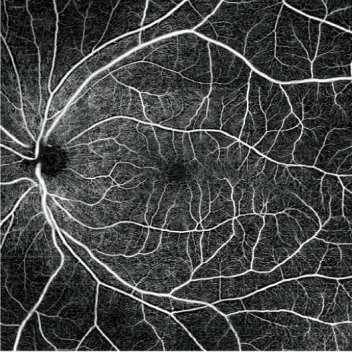

- 高分辨率AngioScan血流OCT圖像

AngioScan(可選軟件)

詳細信息可在AngioScan頁面獲取。